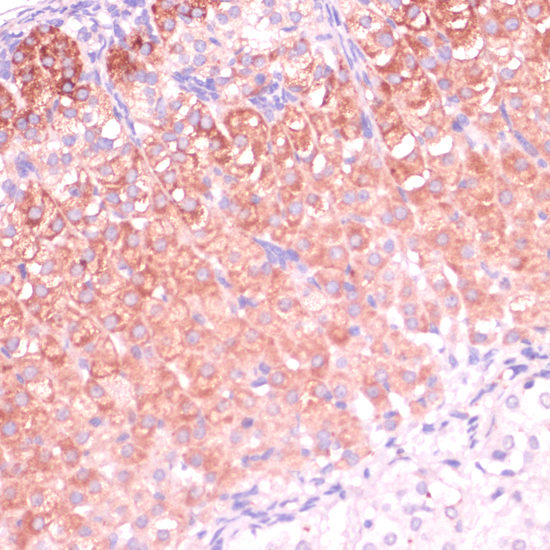

Immunohistochemistry of paraffin-embedded rat adrenal gland using CYP11B2 at dilution of 1:100 (40x lens).

Immunohistochemistry of paraffin-embedded mouse adrenal gland using CYP11B2 at dilution of 1:100 (40x lens).